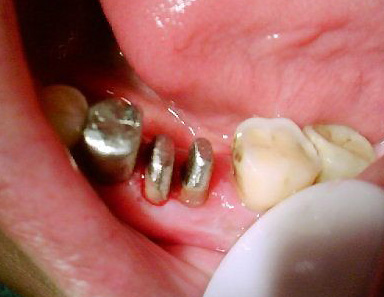

磨牙穿底分根术治疗

图片尺寸680x510